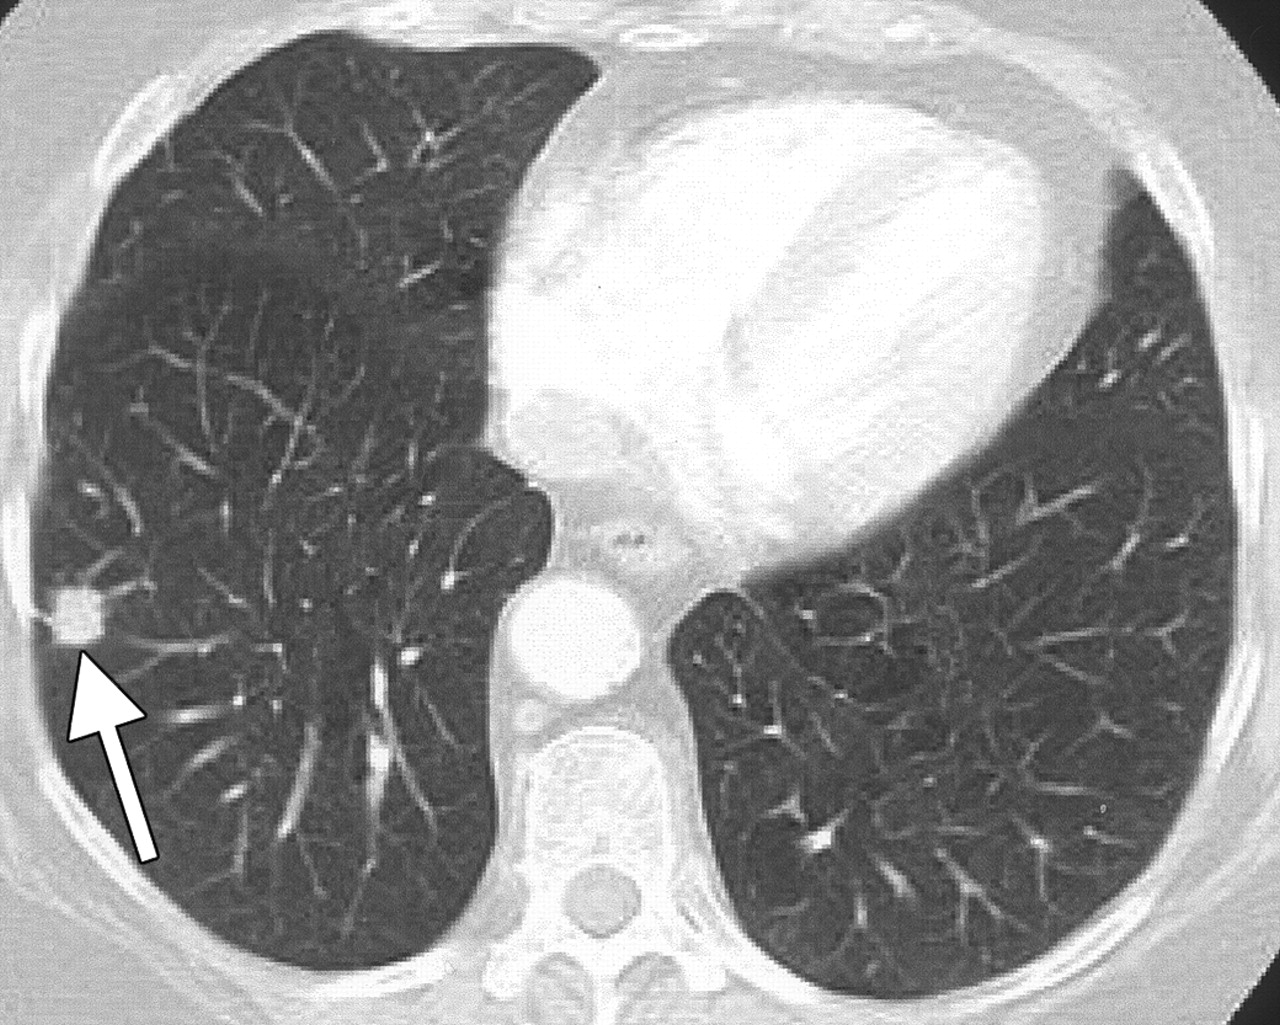

Рак Легких На Кт Фото

Рак Легких На Кт Фото 117 фото